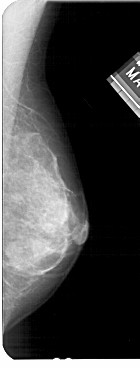

A_1475_1.RIGHT_MLO

RIGHT_MLO LINES 5491 PIXELS_PER_LINE 2086 BITS_PER_PIXEL 12 RESOLUTION 43.5 NON_OVERLAY